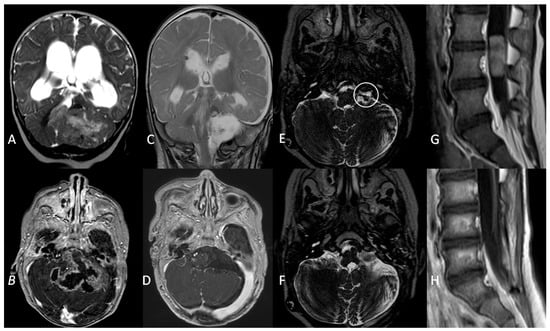

All these patients had anaplastic ependymomas. Three children were treated with GTR resection and chemotherapy, per Italian protocol for paediatric intracranial ependymoma [23]. All children relapsed during follow-up: two patients progressed at 9 and 17 months after diagnosis and died during their fourth year of follow-up. One child progressed 22 months after diagnosis and was alive with no evidence of disease at 52 months of follow-up after surgical resection of a single lumbar metastasis followed by focal radiotherapy (Figure 4).

Figure 4.

A coronal T2W MRI (A) and axial contrast-enhanced T1 W MRI (B) showing a posterior fossa tumour involving the left cerebellopontine angle and extending into the fourth ventricle in a 5-month old infant. (C,D) Three-month follow-up MRI showing complete surgical resection and VP shunt. (E). An axial T2W MRI at 1-year follow-up showing recurrence (white circle) of the tumour in the left lateral recess. (F). Gross total resection of the tumour recurrence. (G). Metastatic dissemination 22 months after diagnosis (single lumbar metastasis). (H). Complete removal of the spinal lesion.

Two children were treated per SIOP Ependymoma I Protocol [22]. The former had metastatic spinal dissemination six months after the GTR surgery and was treated with extensive surgical removal, radiotherapy, and metronomic treatment. Unfortunately, the child died after two years of follow-up because of multiple disease progressions. A GTR was initially achieved in the latter, with subsequent tumour progression at 10 months. A second surgical excision was attempted (GTR) followed by radiotherapy with a stable remnant lesion at 81 months.